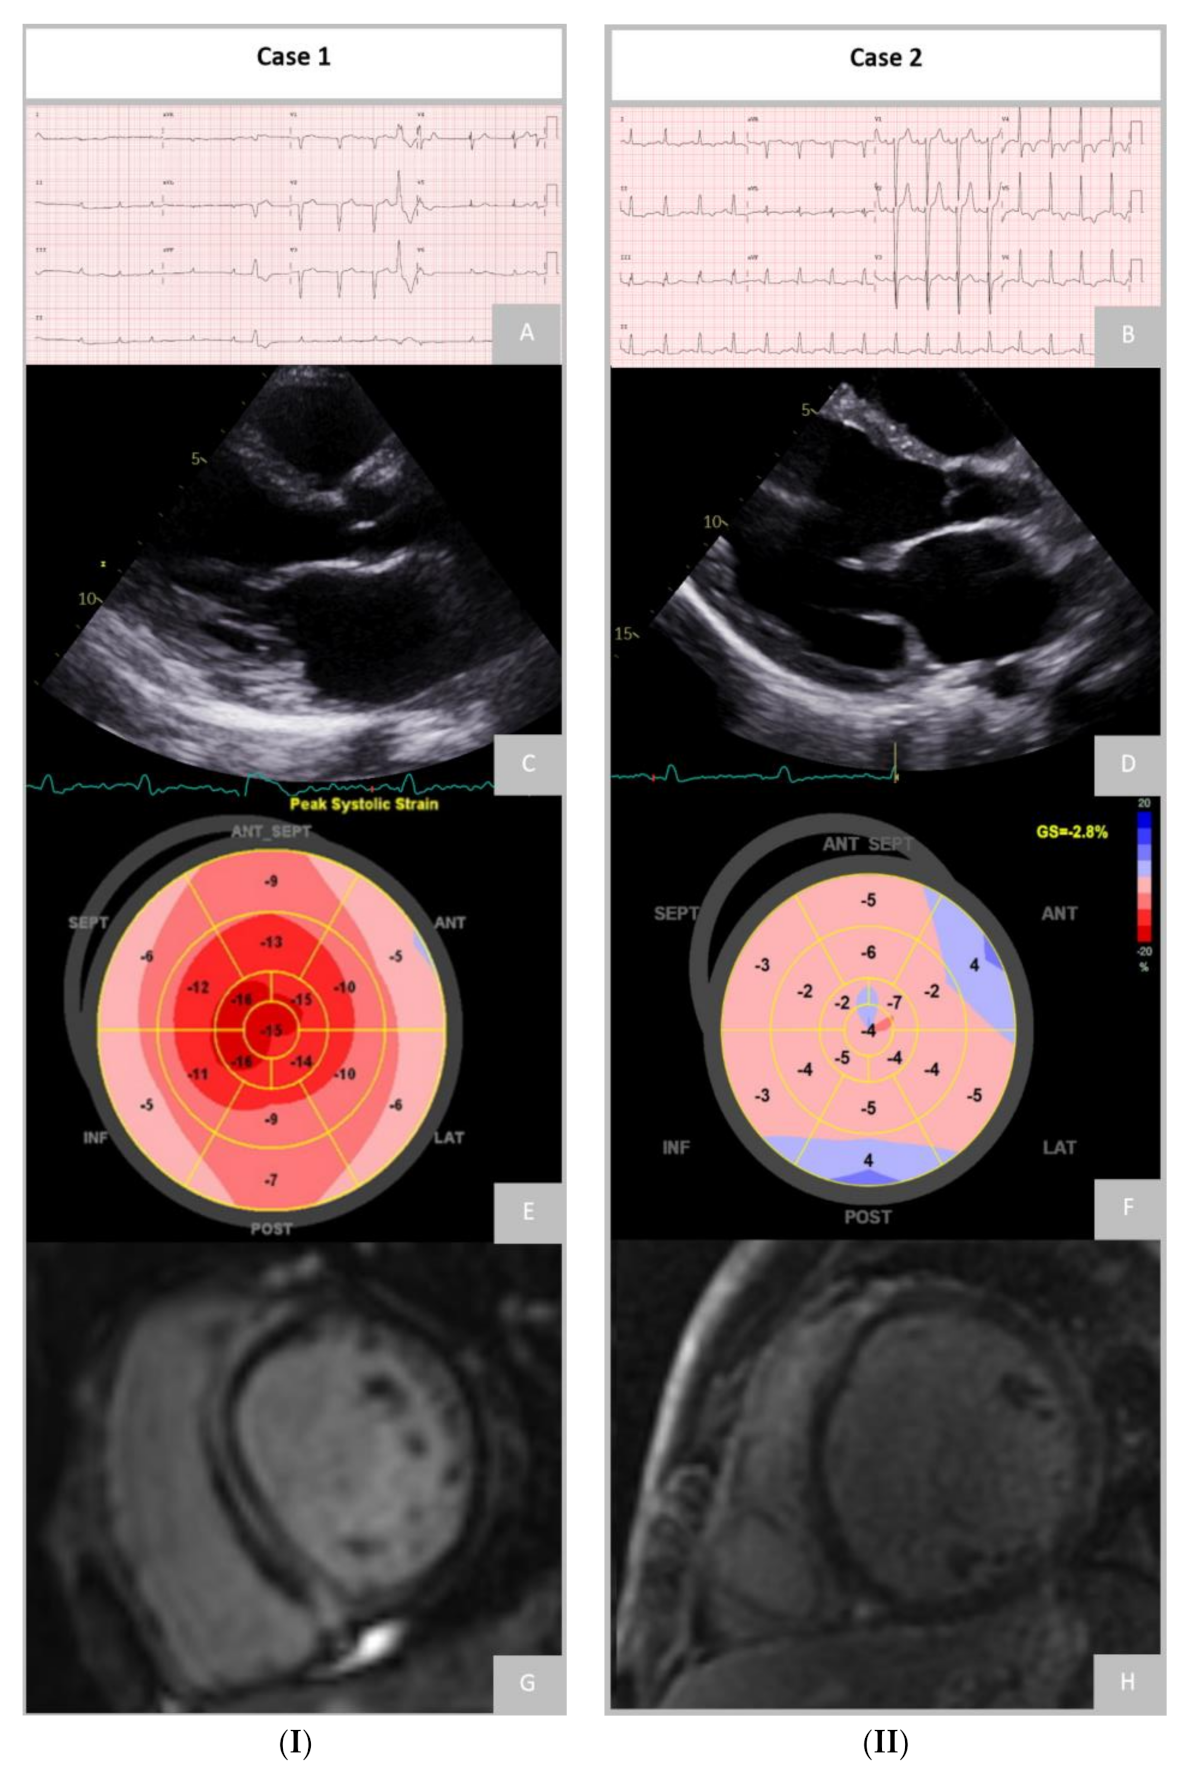

5.1. Electrocardiogram

5.2. Echocardiography

5.3. Cardiac Magnetic Resonance